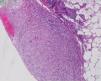

We report a case of a 50-year-old Hispanic male with a longstanding history of Crohn's disease, receiving infliximab therapy for nearly one year, At the time of symptom onset, he was receiving infliximab 5mg/kg every eight weeks with adequate disease control. He presented with progressive shortness of breath and right-sided pleuritic chest pain. Chest computed tomography (CT) revealed a moderate-sized right-sided pleural effusion associated with nodular airspace opacities, without pleural thickening or distinct masses. Repeated thoracenteses yielded exudative fluid with normal glucose and pH, lymphocyte predominance, and low ADA levels; however, Extensive analyses including bacterial cultures, cytology, and a normal serum ACE and calcium results, with negative PET/CT, argued against sarcoidosis, as well as tuberculosis testing (QuantiFERON), was negative. As tuberculosis had been excluded and thoracenteses remained nondiagnostic, a blind pleural biopsy was not pursued. Given the superior diagnostic yield and the advantage of direct pleural visualization, a medical thoracoscopy was performed, revealing diffuse pleural nodularity without distinct masses or adhesions (Fig. 1). Histopathological examination of pleural biopsies demonstrated non-caseating granulomas without malignant cells and staining for acid-fast bacilli and fungi were negative (Figs. 2–5).

Given the absence of other infectious or malignant etiologies, isolated pleural granulomatosis secondary to infliximab therapy was diagnosed. Following discontinuation of infliximab and initiation of vedolizumab, the pleural effusion and symptoms resolved completely within four weeks.